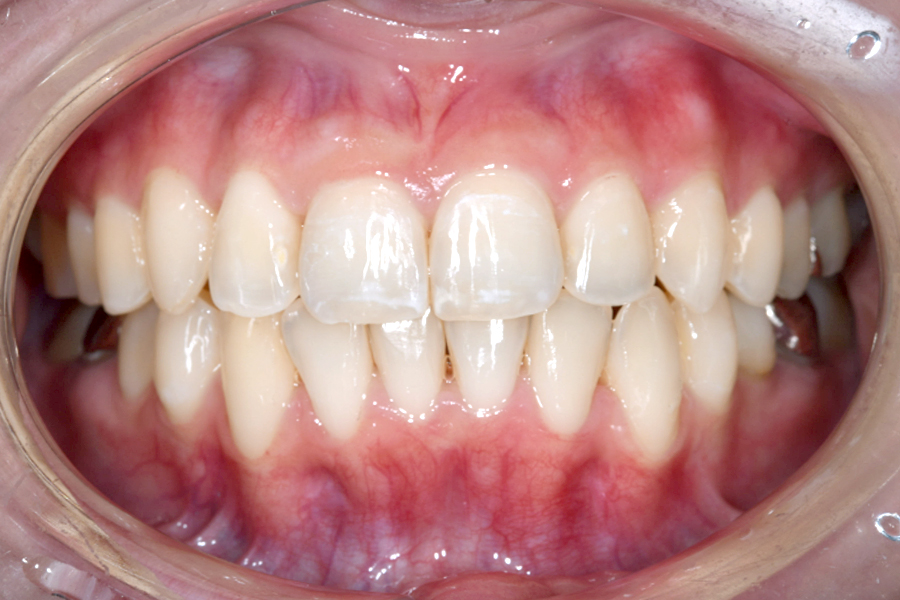

| 主訴 | 歯並びを治したい |

|---|---|

| 治療期間 | 5か月 |

| 治療費 | 部分マウスピース矯正(モニターキャンペーン)と ホワイトニングセット 422,596円(税込) |

| 治療内容 | 目立ちにくいマウスピース矯正 (非抜歯矯正) 歯と歯の間に隙間をつくることにより、歯列弓を広げながら治療を行いました。 また矯正用マウスピースをトレー代わりにし、ジェルを入れてホームホワイトニングを同時に行っております。 |

| 治療のリスク | ・後戻りする可能性があるのでリテーナーを最低でも矯正期間以上はつける必要があります。 ・ホワイトニング後、一時的に痛みが出る場合があります。 |